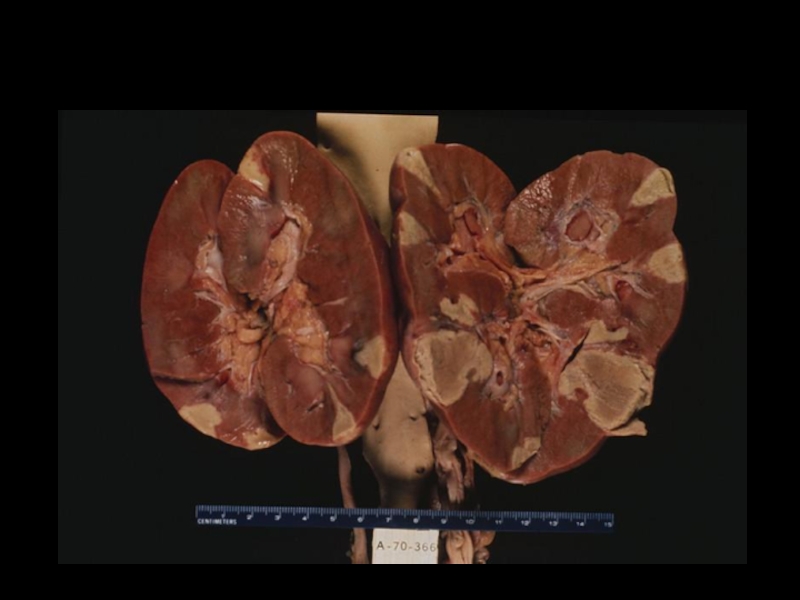

Слайд 20Макропрепаратат Инфаркт селезенки (почки) (описание)

Макропрепаратат  Инфаркт селезенки (почки)  (описание)

Слайд 26Анемический инфаркт почки

№ 1 (окраска гематоксилином и эозином) описание

Анемический инфаркт почки